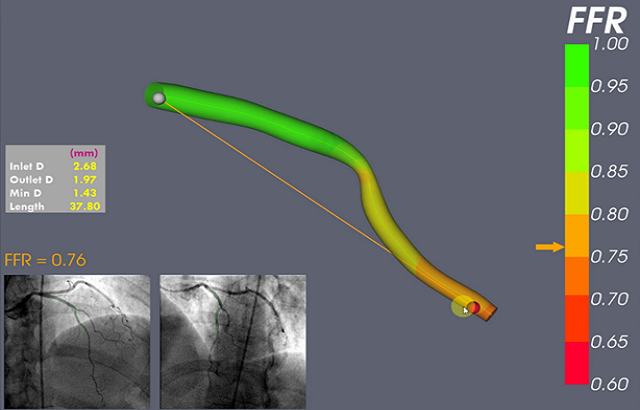

Prof Gunn and his team have developed a computer model called virtual Fractional Flow Reserve (vFFR) that calculates the pressure measurements from pictures of the blood vessels without needing the wire. It could provide greater clinical insight for doctors when making decisions about how to treat coronary artery disease.

Using data collected from hundreds of existing angiograms, the software has been proven to be accurate as tested against real pressure wire measurements. It displays the pressure gradient in colour, a healthy blood pressure gradient being green, and a significant pressure gradient in red.